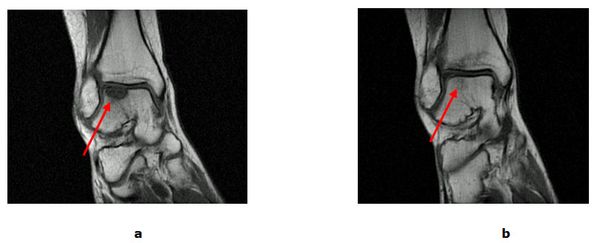

Bei isolierten Knorpel/Knochen Verletzungen (Osteochondrale Läsion, Osteochondrosis dissecans) kann während einer Gelenkspiegelung eine vitalisierende Anbohrung des Knochens erfolgen. Besteht bereits ein ausgeprägter Knorpelschaden wird mit einem speziellen Instrumentarium die harte Knochenschicht durchbrochen und die Bildung von Ersatzknorpel angeregt (Mikrofrakturierung). Der freie Gelenkkörper wird vorher entfernt. Dauerhaft schmerzhafte umschriebene Knorpelläsionen können durch die Verpflanzung eines Knorpel-Knochen-Zylinder (Mosaikplastik, Knorpel-Knochen-Zylinder Transplantation) therapiert werden. Aus einem gesunden nicht belasteten Gelenkanteil wird ein Knorpel-Knochen Zylinder entnommen und in der sog. „Press fit“ Technik am Sprungbein eingesetzt. Ein anderes Verfahren, die sog. MACT eignet sich zur Therapie großer Defektzonen. Bei der MACT (Matrix gekoppelte Autologe Chondrozyten Transplantation) wird Knorpel entnommen und an ein Speziallabor geschickt. Die entscheidenden Zellen werden isoliert, vermehrt und in einer Zweitoperation auf den Knorpeldefekt aufgebracht.

Abb.4: a MRT (Kernspintomografie) vor der Mikrofrakturierung mit Knorpel-Knochen Schaden (Pfeil). b 8 Monate nach erfolgter Therapie mit revitalisiertem Gewebe (Pfeil).